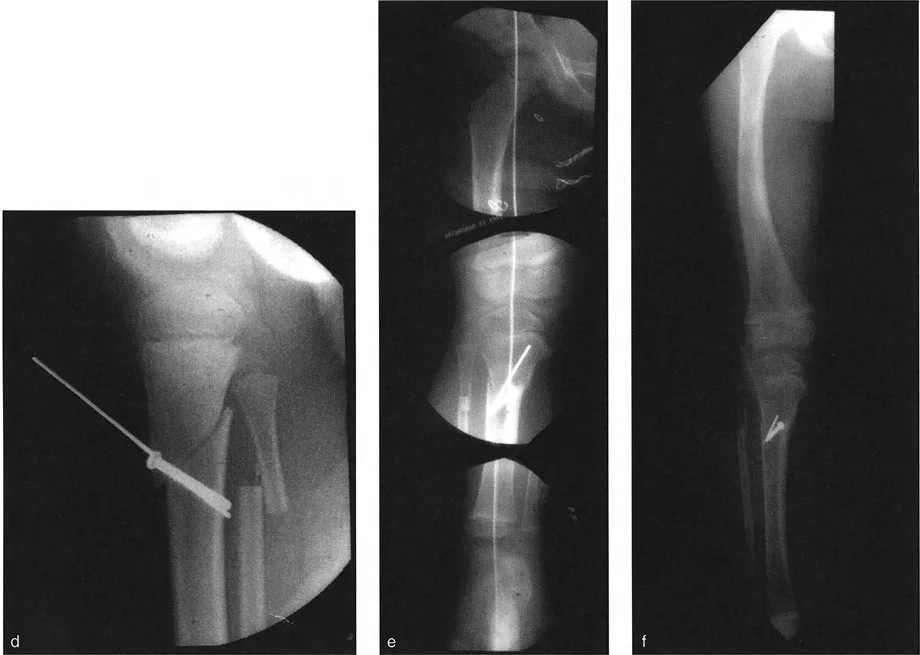

- أشعة الساق الكاملة الواقفة (Standing Long-Leg Radiographs): هذه الأشعة ضرورية. يتم التقاطها والمريض واقفًا لتحميل الوزن على الساقين، مما يسمح بتقييم المحور الميكانيكي للطرف السفلي بالكامل وتحديد مدى انحرافه بدقة. هذه الأشعة تمكن الدكتور هطيف من:

- رسم المحور الميكانيكي.

- تحديد زوايا توجيه المفصل.

- تحديد الموقع الدقيق لمركز دوران الانحراف (CORA) وقاعدة خط التنصيف العرضي (tBL).

- الأشعة السينية التقليدية (AP و Lateral Views): يتم التقاط صور أمامية وخلفية وجانبية للمنطقة المشوهة لتقييم الانحراف الزاوي في المستويات المختلفة.

- دراسات الالتواء بالتصوير المقطعي (CT Scan Torsion Studies): لا يمكن تقييم الدوران بدقة على الأشعة السينية ثنائية الأبعاد. لذا، يتم استخدام التصوير المقطعي المحوسب (CT Scan) لقياس زوايا الالتواء في العظم بدقة عالية، مثل قياس الزاوية بين اللقمتين الفخذيتين الخلفيتين ومحور الكاحل (Bimalleolar Axis).